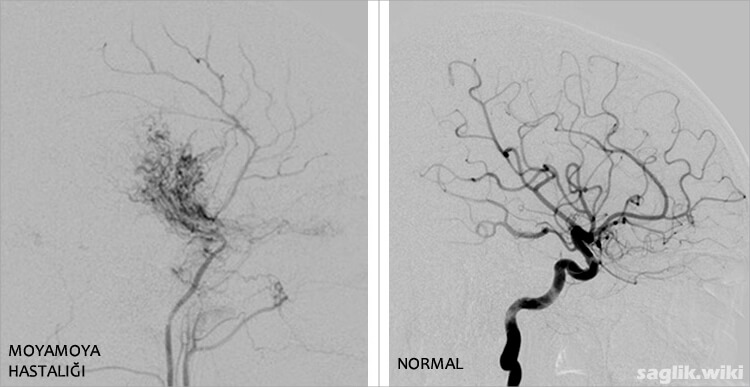

“Moyamoya” Japonca’da “sigara dumanı” anlamına gelir ve tıkanıklığı telafi etmek için oluşan bu küçük damarların anjiyografideki görünümünü tanımlar.

- Serebral anjiyografi: Serebral anjiyografi sırasında, doktorunuz kasıklarınızda uzun ve ince bir tüpü (kateteri) bir damar içine sokar ve X-ışını görüntülemesi kullanarak beyninize yönlendirir. Doktorunuz daha sonra X-ışını görüntülemesi altında görünür hale getirmek için kateterden beyninizin kan damarlarına boya enjekte eder.